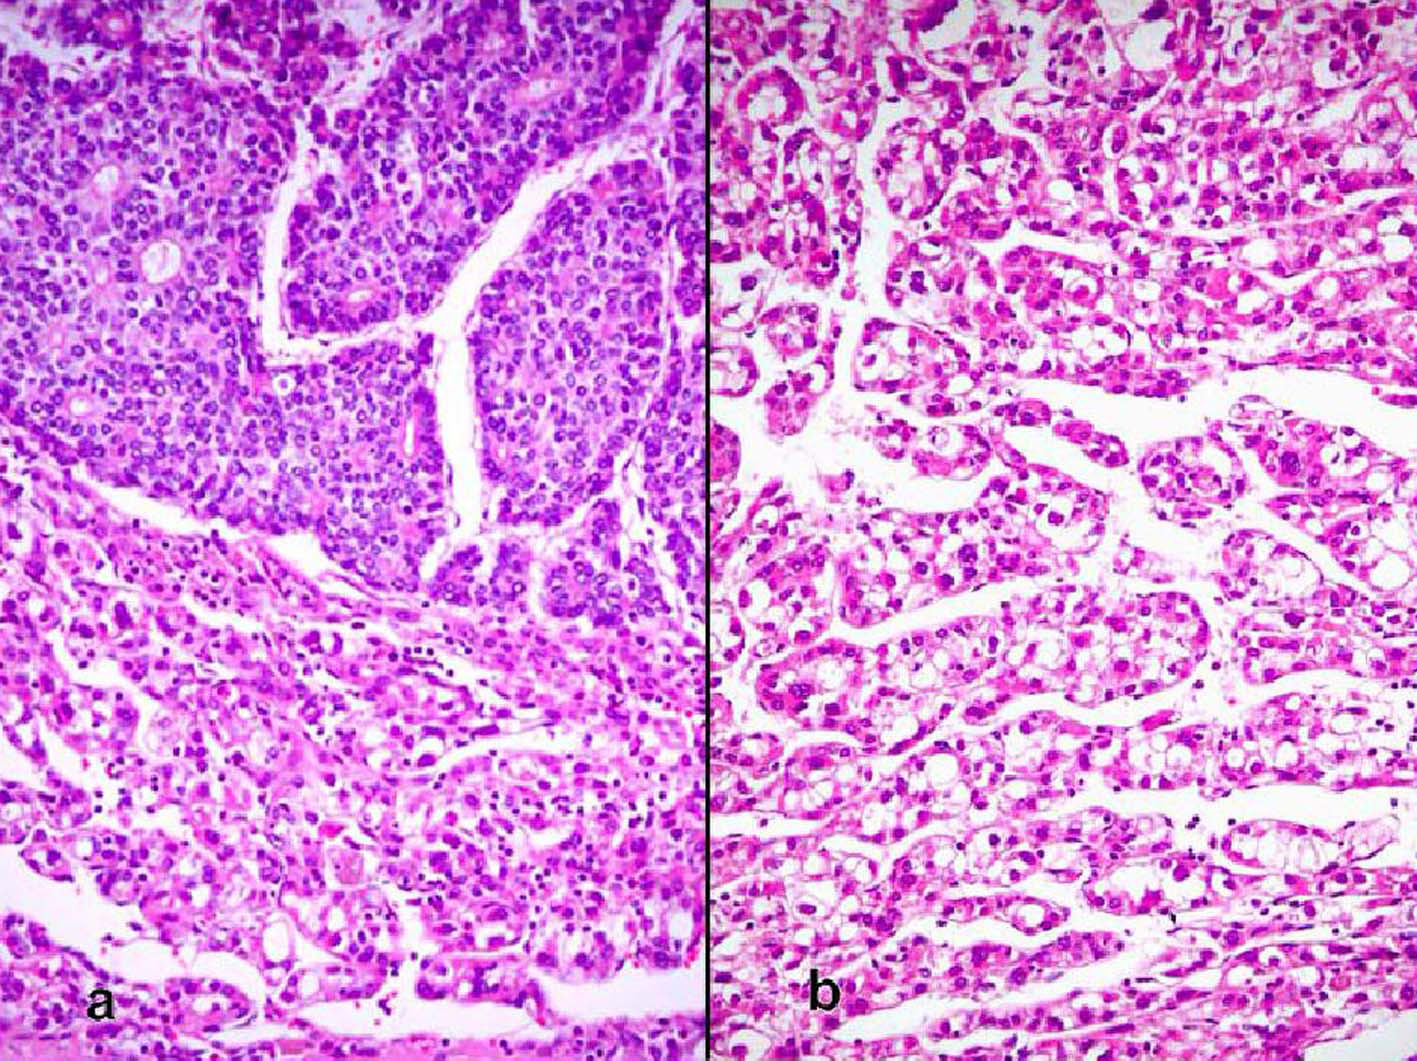

The patient was a 68-year-old Hispanic man who had a medical history of hepatitis B treated with lamivudin monotherapy, which was terminated in 2001. Periodic hepatic ultrasound follow-up showed a mass on the left lobe of the liver. A CT scan of the abdomen revealed a 4.0 cm mass located in the hepatic segment IV (Fig. 1). The serum level of alpha-fetoprotein (AFP) at this time was 1,191 ng/ml. The patient had normal liver enzymes and total bilirubin of 0.4 mg/dl. CA19-9 and CA125 were normal. CT of chest and extrahepatic abdomen showed no other lesions. At our institution, a liver core biopsy was performed, which showed an extensively necrotic, epithelial malignant neoplasm (Fig. 2). An intraoperative ultrasound showed that the mass was located in segment IV extending to segment V for which an extended left hepatectomy was performed. Intraoperatively, the abdominal cavity, including omentum, peritoneum, intestines, stomach, and pancreas, were free of lesions. The specimen showed both a hepatocellular carcinoma and a neuroendocrine carcinoma (Fig. 3), confirmed by immunohistochemistry exam (Fig. 4). The patient was treated with four courses of chemotherapy regimen including Etoposide: 120 mg/m2 day 1 to day 3 and cisplatin: 80 mg/m2 day 2; the cycle was repeated every three weeks. The patient is free of recurrence with a follow-up of 28 months.

![]() Click for large image | Figure 3. (a) Sharp demarcation of the both components of the moderately differentiated hepatocellular carcinoma and the neuroendocrine carcinoma with the latter showing rosettes (hematoxylin and eosin, × 100). (b) Hepatocellular carcinoma (hematoxylin and eosin, × 200). |